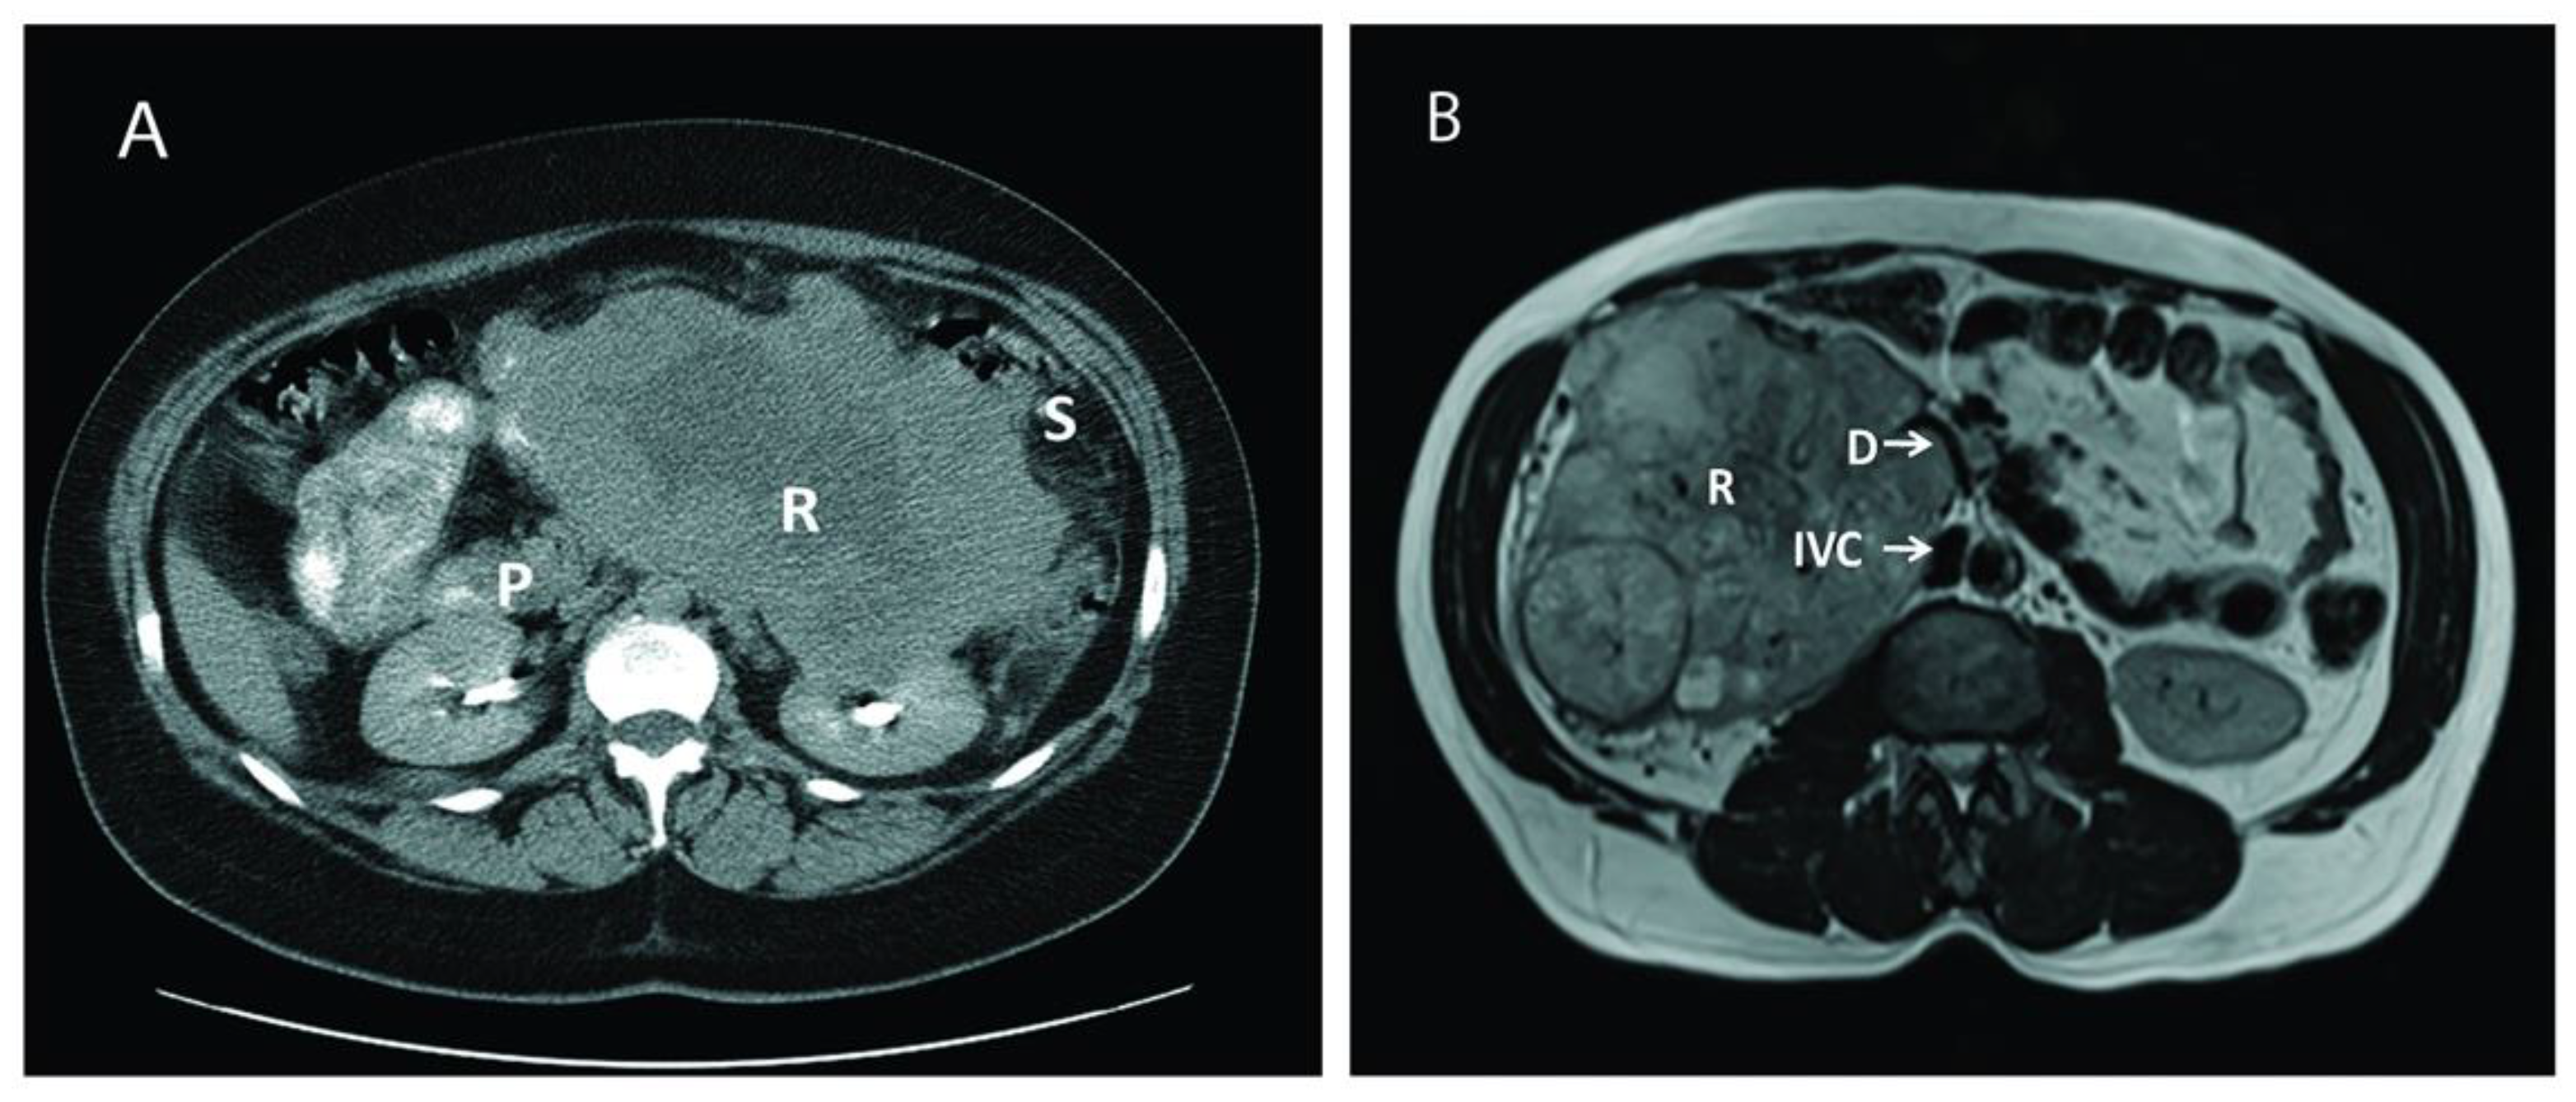

After obtaining Institutional Review Board approval and following the ethical principles of the Helsinki Declaration (as revised in 2013), a retrospective chart review was performed on 18 consecutive patients who underwent surgical treatment for large, aggressive, locally advanced RCC cases between June 2003 and November 2019 at our institution. All relevant data on demographics, clinical presentation, disease characteristics, surgical details, and postoperative complications were collected and analyzed. Postoperative complications were assessed using the Clavien-Dindo Classification System [11], and defined as occurring within a 30-days period of the intervention date. Overall survival (OS) was ascertained by the review of medical records or using the Social Security Death Index (SSDI) database [12] when necessary. Abdominal computed tomography and/or magnetic resonance imaging were used to diagnose the renal tumor, delineate the tumor thrombus inside the inferior vena cava, and depict the extent of the invasion to adjacent organs (Figure 1).

Figure 1.

Computed tomography (CT) and magnetic resonance imaging (MRI) of two different patients with large renal mass. (A): CT of a large left renal mass with lack of soft tissue planes between pancreas, spleen, and splenic flexure; (B): MRI of a right large solid and cystic enhancing mass replacing the right renal parenchyma with mass effect and compression of proximal duodenum. P: Pancreas; R: Renal Tumor; S: Splenic flexure of colon; IVC: Inferior Vena Cava: D: Duodenum.